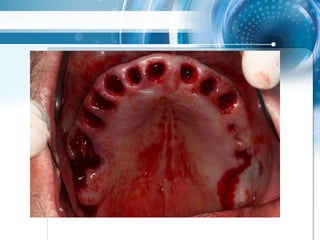

Triple scan Technik

• Multiple Änderungen von Modellsituation nach CT

scan, Extraktionen und Wurzelfüllungen realisiert,

4 geplante Extraktionen

2 mm guide, multiple Extraktionen mit

zahngestütytem drill guide über 3

Zähnen als strategischer Support

Triple scan Technik •Multiple Änderungen von Modellsituation nach CT scan, Extraktionen und Wurzelfüllungen realisiert, 4 geplante Extraktionen

• 58.

2 mm guide,multiple Extraktionen mit zahngestütytem drill guide über 3 Zähnen als strategischer Support